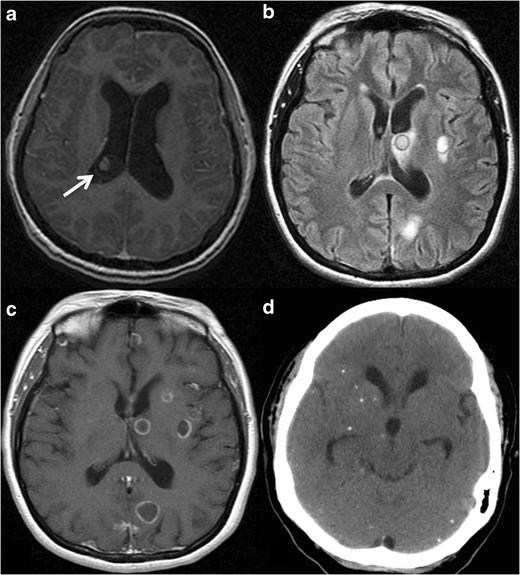

Radiologists seldom encounter parasitic diseases in their daily practice in most of Europe, although the incidence of these diseases is increasing due to migration and tourism from/to endemic areas. Moreover, some parasitic diseases are still endemic in certain European regions, and immunocompromised individuals also pose a higher risk of developing these conditions. This article reviews and summarises the imaging findings of some of the most important and frequent human parasitic diseases, including information about the parasite's life cycle, pathophysiology, clinical findings, diagnosis, and treatment. We include malaria, amoebiasis, toxoplasmosis, trypanosomiasis, leishmaniasis, echinococcosis, cysticercosis, clonorchiasis, schistosomiasis, fascioliasis, ascariasis, anisakiasis, dracunculiasis, and strongyloidiasis. The aim of this review is to help radiologists when dealing with these diseases or in cases where they are suspected. Teaching Points • Incidence of parasitic diseases is increasing due to migratory movements and travelling. • Some parasitic diseases are still endemic in certain regions in Europe. • Parasitic diseases can have complex life cycles often involving different hosts. • Prompt diagnosis and treatment is essential for patient management in parasitic diseases. • Radiologists should be able to recognise and suspect the most relevant parasitic diseases.

在欧洲大部分地区,放射科医生在日常工作中很少遇到寄生虫病,尽管由于往返于流行地区的移民和旅游活动,这些疾病的发病率正在上升。此外,某些寄生虫病在欧洲的某些地区仍然流行,免疫功能低下的个体感染这些疾病的风险也更高。本文回顾并总结了一些最重要且常见的人类寄生虫病的影像学表现,包括有关寄生虫生命周期、病理生理学、临床表现、诊断和治疗的信息。我们涵盖了疟疾、阿米巴病、弓形虫病、锥虫病、利什曼病、棘球蚴病、囊尾蚴病、华支睾吸虫病、血吸虫病、片形吸虫病、蛔虫病、异尖线虫病、麦地那龙线虫病和粪类圆线虫病。这篇综述的目的是在放射科医生处理这些疾病或怀疑患有这些疾病的病例时提供帮助。教学要点 • 由于人口迁移和旅行,寄生虫病的发病率正在上升。 • 某些寄生虫病在欧洲的某些地区仍然流行。 • 寄生虫病可能具有复杂的生命周期,通常涉及不同的宿主。 • 及时诊断和治疗对于寄生虫病患者的管理至关重要。 • 放射科医生应该能够识别和怀疑最相关的寄生虫病。